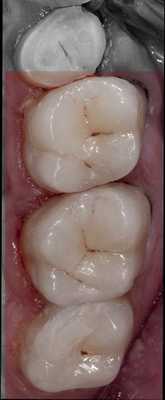

На рисунке 12 показана исходная ситуация.

На рисунках 13—15 показано послойное внесение материала в полость: слой дентина, слой хроматической эмали (композит распределяется по полости без полимеризации), слой поверхностной эмали.